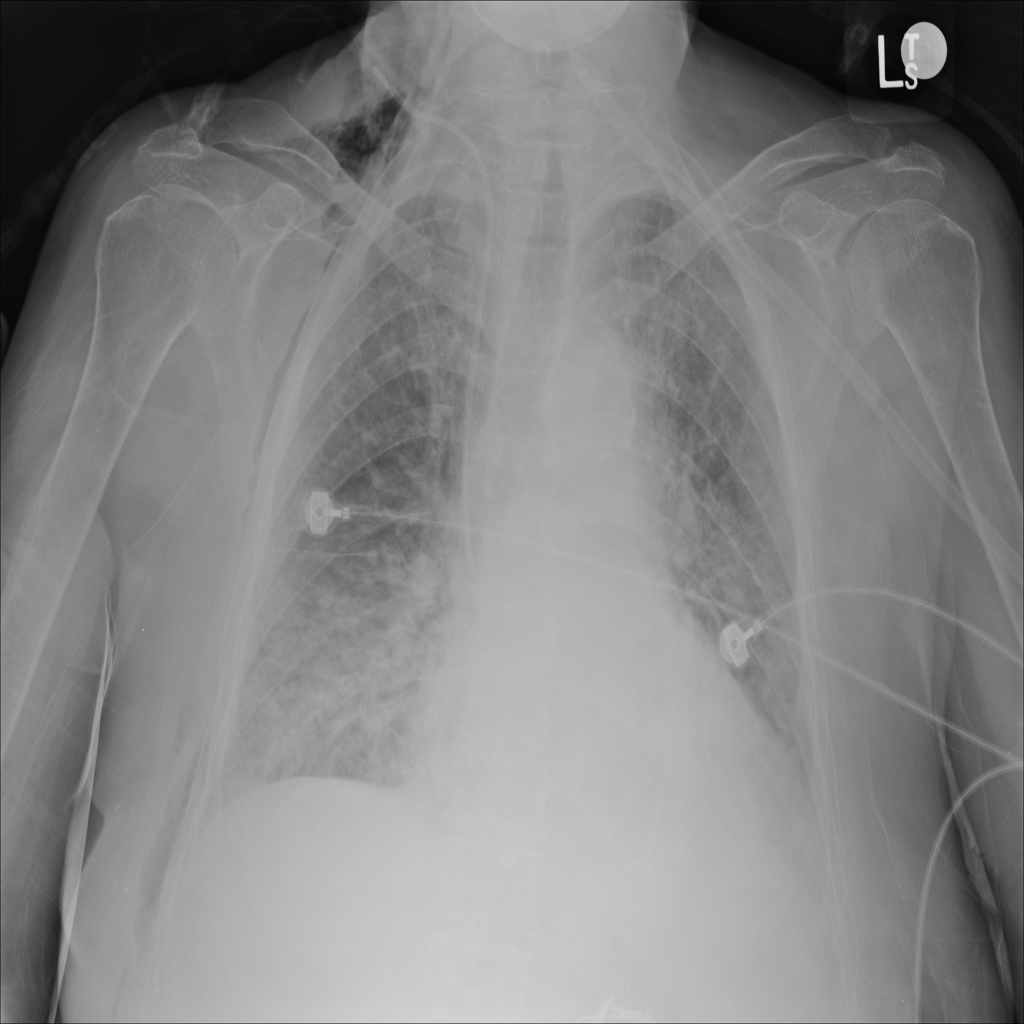

Showing up to 90 reference images for Emphysema.

PAT-FEC4 · IMG-000Emphysema

PAT-FEC4 · IMG-000

PA